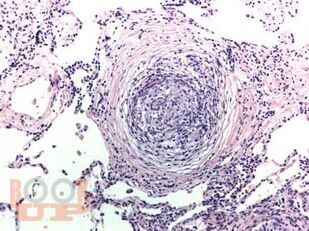

Учебное пособие предназначено для ординаторов, обучающихся по специальности 31.08.49 Терапия и слушателей дополнительного профессионального образования. В настоящем учебном пособии изложены современные представления по распространенности, этиологии, патогенезу, клинике, диагностике, дифференциальной диагностике и лечению саркоидоза органов дыхания, кожных покровов, почек, кардиального и костно-мышечного саркоидоза. Имеются тестовые задания и ситуационные задачи для самоконтроля знаний, издание иллюстрировано рисунками, схемами и таблицами.